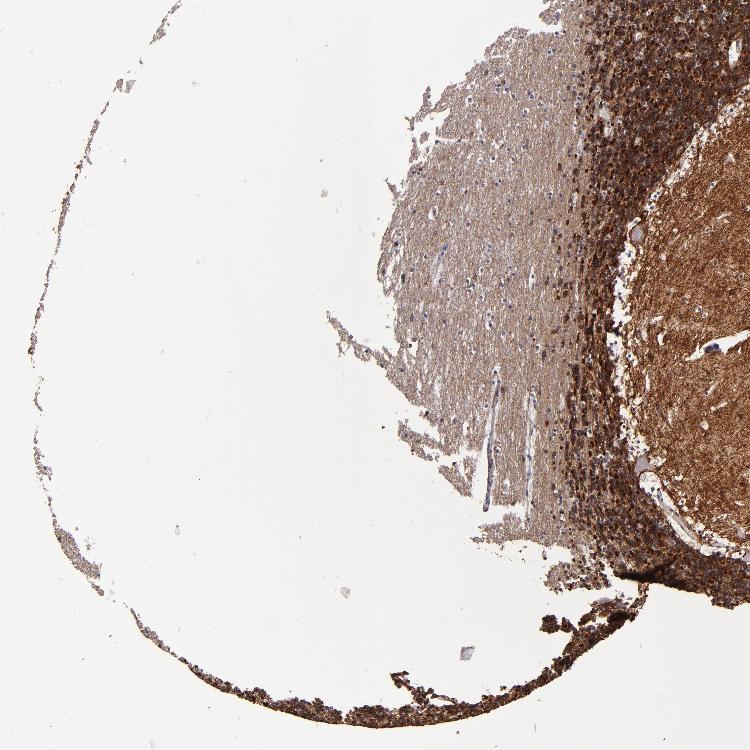

CEREBELLUM - Antibody stainingi

Antibody staining in the annotated cell types in the current human tissue is reported as not detected, low, medium, or high, based on conventional immunohistochemistry profiling in selected tissues. This score is based on the combination of the staining intensity and fraction of stained cells.

Each image is clickable and will lead to virtual microscopy that enables deeper exploration of all samples and also displays staining intensity scores, fraction scores and subcellular localization as well as patient and tissue information for each sample.

Antibody HPA054437Antibody HPA058511Antibody CAB002776Antibody CAB015122

Bergmann glia - cytoplasm/membrane -Not detected--

Bergmann glia - nucleus -Not detected--

GLUC cells - cytoplasm/membrane -Not detected--

GLUC cells - nucleus -Not detected--

Purkinje cells Not detected-MediumMedium

Purkinje cells - cytoplasm/membrane -Not detected--

Purkinje cells - dendrites -Not detected--

Purkinje cells - nucleus -Not detected--

Cells in granular layer High-HighHigh

Cells in molecular layer Not detected-MediumHigh

Granular cells - cytoplasm/membrane -Not detected--

Granular cells - nucleus -Not detected--

Molecular layer - neuropil -Medium--

Molecular layer cells - cytoplasm/membrane -Not detected--

Molecular layer cells - nucleus -Not detected--

Processes in granular layer -Not detected--

Processes in molecular layer -Not detected--

Processes in white matter -Not detected--

Synaptic glomeruli - capsule -Not detected--

Synaptic glomeruli - core -High--

White matter cells - cytoplasm/membrane -Not detected--

White matter cells - nucleus -Not detected--